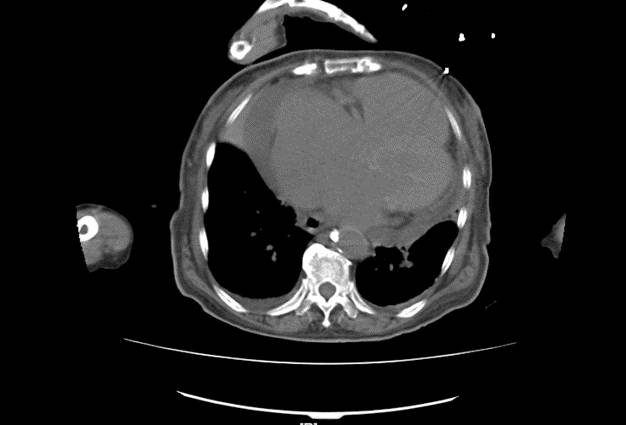

胸部+全腹平扫CT

1、双肺炎症性改变,双侧胸腔积液

2、心影增大,心包积液

3、动脉硬化

4、大量腹水,胆囊壁增厚,

5、下腔静脉增宽